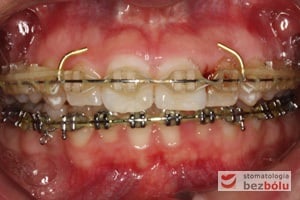

Leczenie bezekstrakcyjne z wykorzystaniem strippingu

Pacjentka lat 22 zgłosiła się do naszej placówki celem podjęcia leczenia ortodontycznego. Głównym oczekiwaniem pacjentki była poprawa estetyki uśmiechu oraz brak ekstrakcji zębów na drodze do jej uzyskania. Ze względu na liczne stłoczenia zębów w górnym i dolnym łuku, dość duży materiał zębowy w porównaniu z bazą kostną, a także zgryz przewieszony boczny prawostronny po dokładnej analizie cefalometrycznej oraz analizie modeli diagnostycznych zastosowano leczenie bezekstrakcyjne z wykorzystaniem strippingu jako alternatywy dla usuwania zębów, mającego na celu uzyskanie miejsca w łuku na uszeregowanie zębów. Po fazie aktywnego leczenia trwającego 18 miesięcy zastosowano leczenie retencyjne w postaci szyny retencyjnej w łuku górnym oraz retainera stałego w łuku zębowym dolnym klejonego od kła do kła.